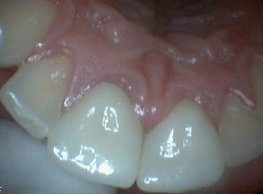

Zirconia Anterior Crowns